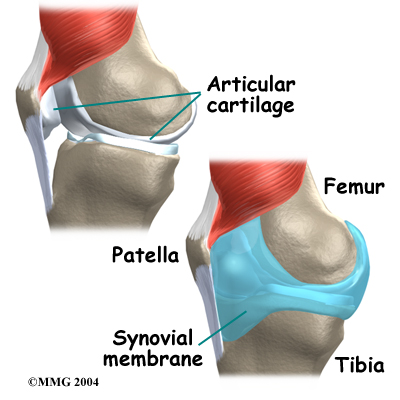

The knee joint is formed where the thighbone (femur) meets the shinbone (tibia). A slick cushion of articular cartilage covers the ends of both of these bones so that they slide against one another smoothly. The articular cartilage is kept slippery by joint fluid made by the joint lining (synovial membrane). The fluid is contained in a soft tissue enclosure around the knee joint called the joint capsule.

The kneecap (patella) is the moveable bone on the front of the knee. It is wrapped inside a tendon that connects the large muscles on the front of the thigh (the quadriceps muscles) to the tibia. The back of the patella is covered

with articular cartilage. The patella glides within a groove on the front of the femur.